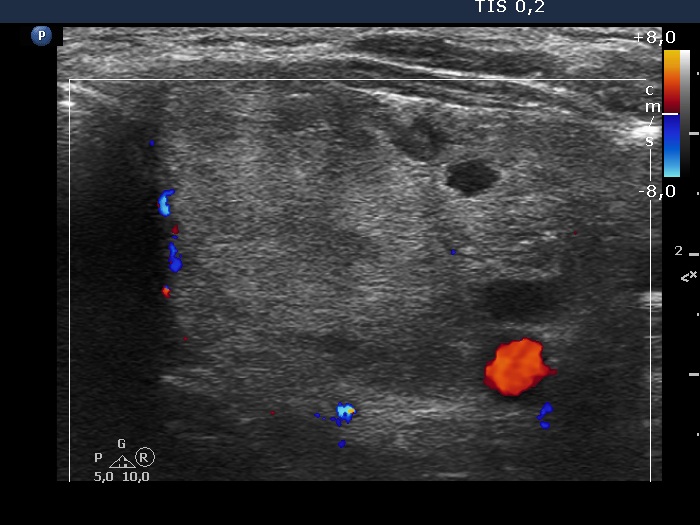

Left lobe, longitudinal scan, color Doppler mode. The lesion is almost avascular.